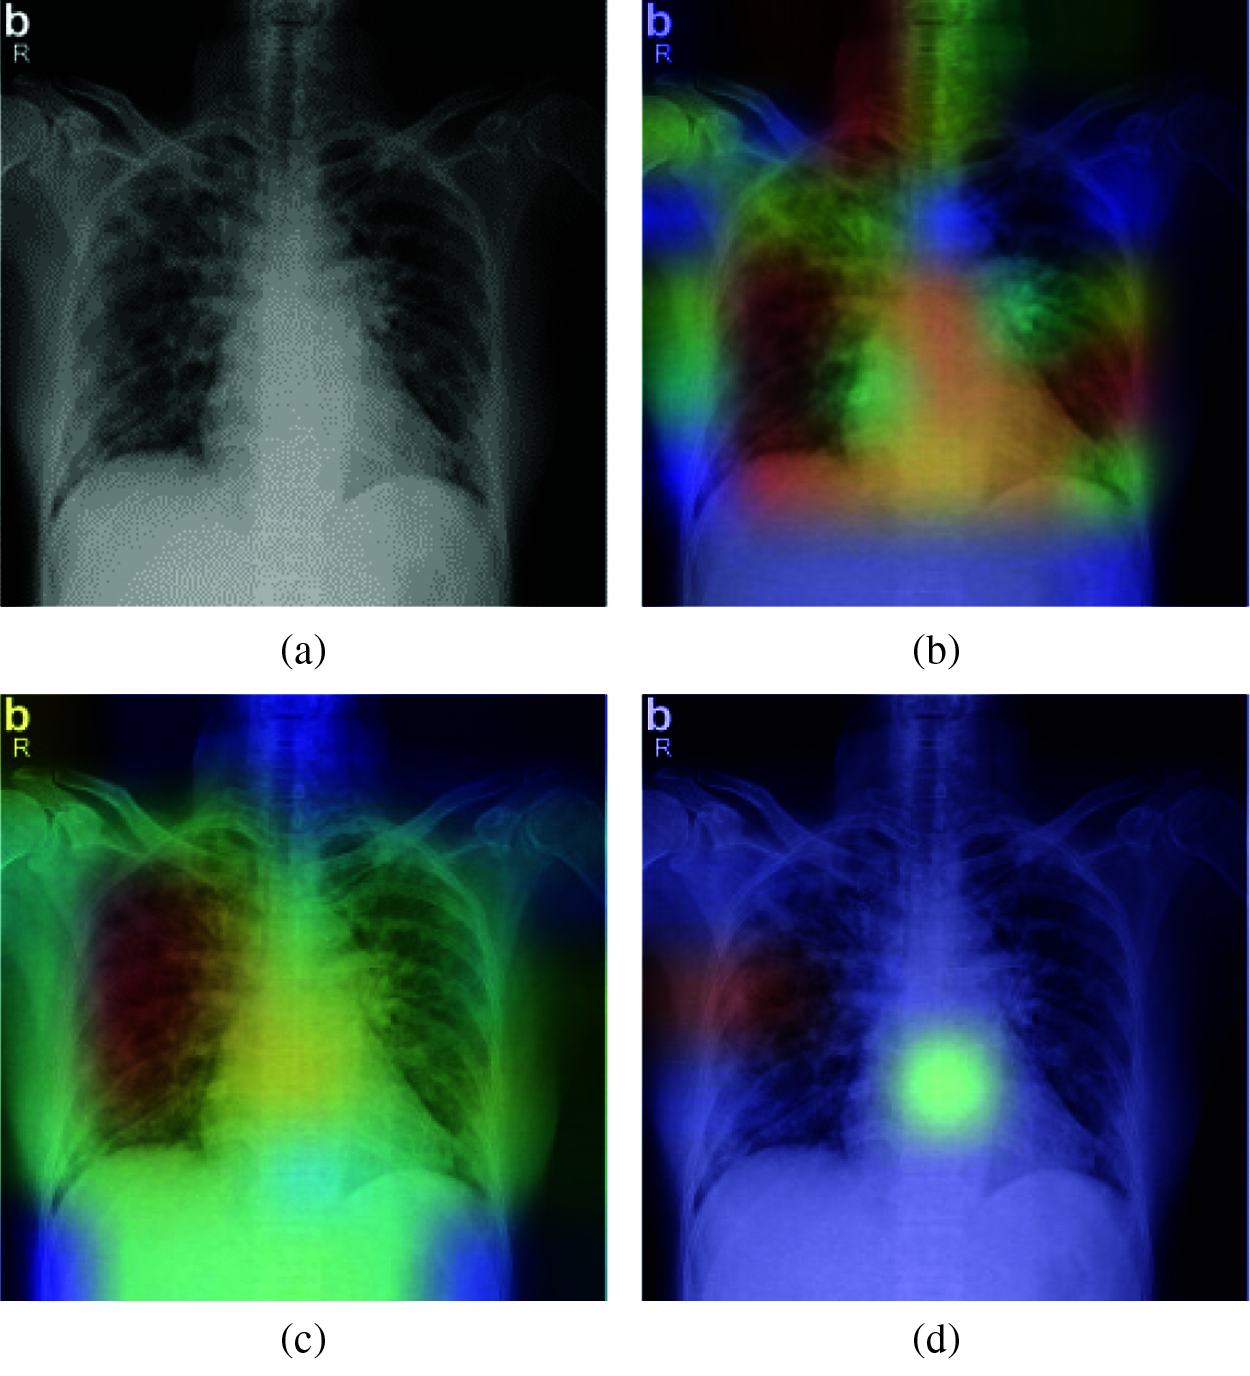

CNN models are generally a black box tool in terms of image processing across layers. Selvaraju et al. [35] proposed Grad-CAM as an interesting approach for debugging almost any CNN model Based on locating and processing the gradient of the target for the last convolutional layer, this methodology provides us with a heat-map to visualize how the model is processing our dataset and which regions of the images contribute the most to the prediction decision. This technique consists of tracking prediction process based on the last convolutional layer. Weighted sum of the feature maps is performed for each prediction in order to detect the principle areas of the original image that actually affects the model decision. The result is a kind of heat map that could be associated to the original image for visualization. This technique helps to determine whether the model predicts the COVID-19 case based on the correct infected region of the chest or not. Fig. 18 shows a real COVID-19 X-ray tested for prediction by different CNN models.

Figure 18: Grad-CAM visualization for predicting a real case of COVID-19: (a) Original case (True class: COVID-19), (b) VGG-19 (Predicted class: COVID-19), (c) VGG-16 (Predicted class: COVID-19), (d) MobileNetV2 (Predicted class: Normal)

The results of the prediction experiment show that the VGG19 and VGG16 models correctly predicted the case, and the Grad-CAM visualization confirmed that the prediction was based on the correct regions in the lungs. The MobileNetV2 model predicted the case as normal, and the Grad-CAM visualization of this model showed that the prediction was based on a small region of the X-ray image, which explains the result.